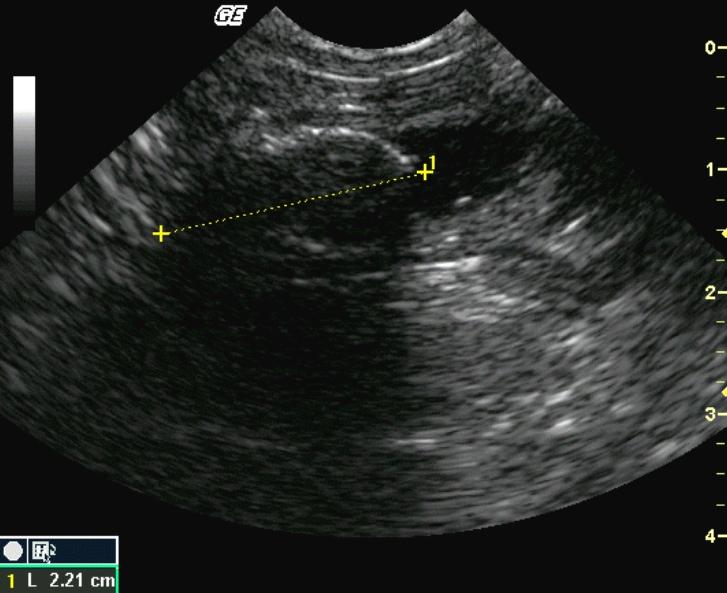

This 4-year-old MN Himalayan cat was presented for 3 days of persistent vomiting, lethargy, and anorexia. The physical exam revealed moderate dehydration and tense abdomen; the cat would not allow deep palpation. The CBC revealed moderate leukocytosis with a left shift. Blood chemistry demonstrated moderate azotemia, mild hyperglycemia, mild hyponatremia and hypochloremia. The urine was concentrated with minor proteinuria.